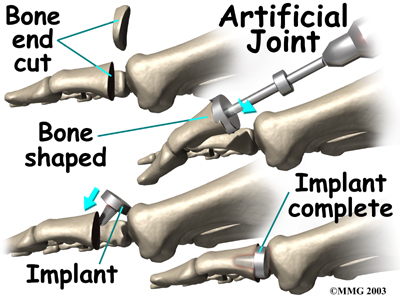

Some surgeons prefer replacing the joint with an artificial joint, similar to what is done in the knee or hip, only much smaller. Replacing the joint with an artificial joint is usually recommended for moderately involved joints. (Many surgeons, however, believe that arthrodesis or fusion still produces better results for patients with severe hallux rigidus.)

In this procedure, one of the joint surfaces is removed and replaced with a plastic or metal surface. This procedure may relieve the pain and preserve the joint motion. The major drawback to this procedure is that the artificial joint will probably not last a lifetime and will require more operations later if it begins to fail.

To perform an artificial joint replacement, an incision is first made on the top of the big toe over the MTP joint. Once the joint is surgically entered, the arthritic joint surface of the proximal phalanx (the first bone of the big toe) is removed. The hollow marrow area of the proximal phalanx is prepared with special instruments so that the artificial joint surface will fit snugly into the bone. Different sized implants are tried, and the toe is moved through a range of motion to help determine if the fit is proper.

Once the surgeon is satisfied that everything fits, the artificial joint surface is implanted. The joint capsule and skin incision are then closed with small stitches.

There are actually several different ways to accomplish a joint replacement for hallux rigidus. A total joint replacement removes and replaces both sides of the joint. This type of procedure requires a conical stem that sits down inside the toe bones on either side of the joint. The implants can be made of ceramic, titanium, cobalt-chrome, or titanium combined with polyethylene (plastic) parts.

Metatarsal hemiarthroplasty replaces just one side of the joint; the one between the bone closest to the middle part of the foot (metatarsal) and the middle phalangeal bone. Limited studies have been done using this approach but patient satisfaction is reportedly high with few implant failures or need for revision surgery.